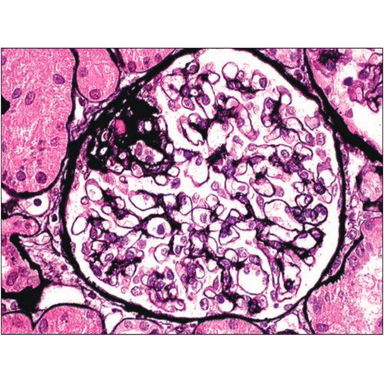

Kidney FSGS